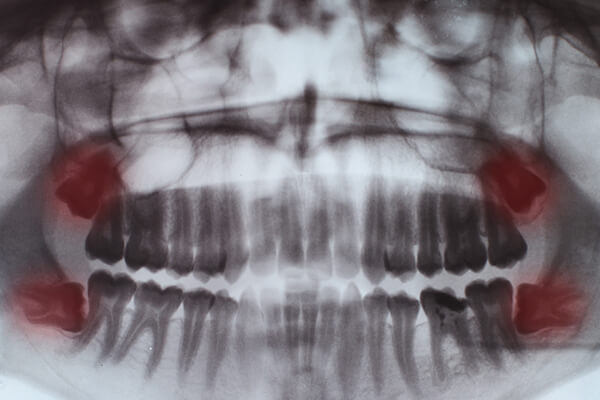

Galería de antes y después